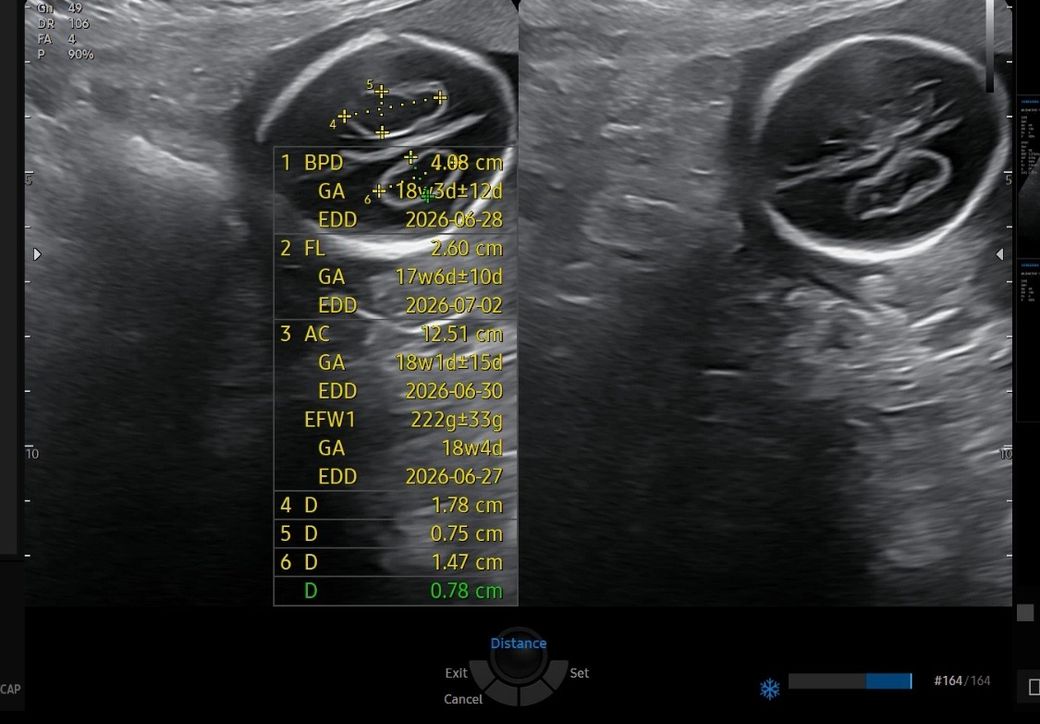

17주 맥락총낭종(물혹) 관련 소견

사진에 보이는 검은 부분이 물혹 크기인걸까요?

• 1번 째 사진

제공하신 초음파는 임신 17주 전후에 흔히 확인되는 맥락총낭종(choroid plexus cyst, CPC) 소견으로 보입니다.

사진에서 머리 안쪽에 보이는 검은 타원형 구조가 낭종 자체이며, 주변의 밝은 구조는 뇌실과 맥락총입니다. 화면에 표시된 수치 중 D 1.78 cm, 1.47 cm, 0.78 cm 등은 낭종의 장·단경을 여러 방향에서 잰 값으로 보이며, 가장 크게 보이는 검은 영역 전체가 모두 하나의 낭종이라기보다는 절단면과 각도에 따라 낭종과 뇌실 공간이 함께 보이는 경우가 많습니다. 따라서 육안상 “너무 커 보인다”는 인상만으로 크기를 판단하는 것은 정확하지 않습니다.

정리하면, 사진에 보이는 검은 부분은 맥락총낭종에 해당할 가능성이 높고, 크기가 다소 커 보이더라도 단독 소견이라면 예후는 대부분 양호합니다. 현재 단계에서는 주치의가 다른 구조 이상이 없다고 설명했다면 경과 관찰이 일반적입니다. 그리고 상기 내용을 기억해두시고 주치의가 이런 검사해보자고 말씀하시면 잘 따라가시면 큰 문제 없이 해결될겁니다.